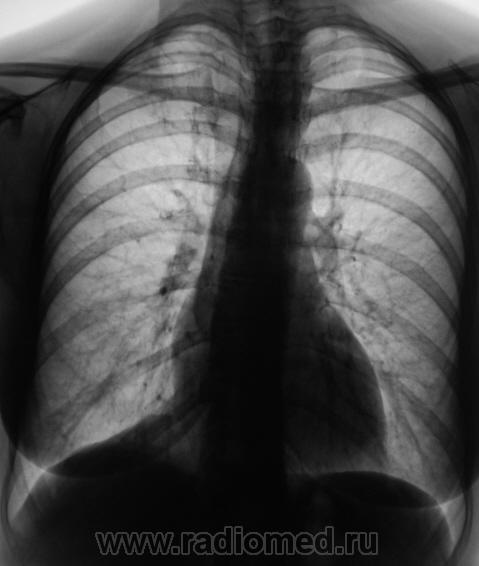

Пол пациента: Мужской пол Тип патологии: Инфекция Область исследования: Грудная клетка и верхние дыхательные пути Методы исследования: Rg После прохождения флюорографии взяли пациента на контроль, дообследовали и направили к коллегам-фтизиатрам. Пациент жалоб не предъявляет. Ваше мнение коллеги? Чт, 24/12/2009 - 14:18 #1 serega Не на сайте Был на сайте: 12 лет 4 месяцев назад Зарегистрирован: 15.10.2009 - 18:10 Публикации: 99 Здравствуйте, Валентин Львович. Тут по моему tbs. А почему Вы "боковушки" не наврезали? Или Вы посчитали, что и так всё ясно? Чт, 24/12/2009 - 14:26 #2 Катенёв Валенти... Не на сайте Был на сайте: 7 лет 3 недели назад Зарегистрирован: 22.03.2008 - 22:15 Публикации: 54876 Здравствуйте уважаемый serega ! Клиника типична - "клиники никакой", жалоб нет. Скиалогия также типичная, сомнений по поводу "очагового" не было. Выполнили "фтизиатрический стандарт" и отдали фтизиатрам.

Клиника типична - "клиники никакой", жалоб нет. Скиалогия также типичная, сомнений по поводу "очагового" не было. Выполнили "фтизиатрический стандарт" и отдали фтизиатрам.